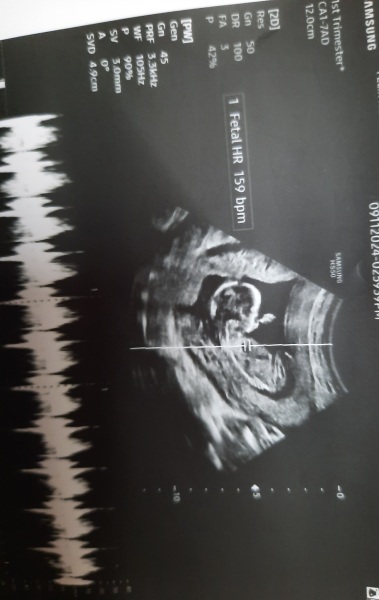

Hello, yesterday i have an ultrasound and im 12 weeks 5 days!!! I would like to ask you your opinion about the gender ! Thank you in advance ❤️

❤️ thank you !! I hope for

a little girl ! Because if you see the scan I rhink

that the nub is stalked and I think that its

a male trait development